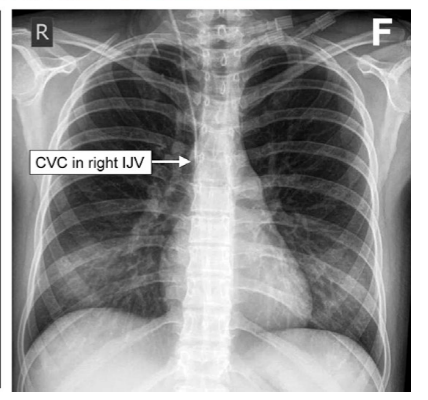

在导管放置之前,可以用系列胸部X线摄影代替透视来确认导丝的位置,但是这种操作可能比较麻烦,可能会增加感染机会。平片可常规用于检查置入后的IJV和SCV CVC的定位,并排除气胸或胸腔积液,尽管这种做法在超声引导置入的时代受到质疑,但为了安全,可作为常规检查。